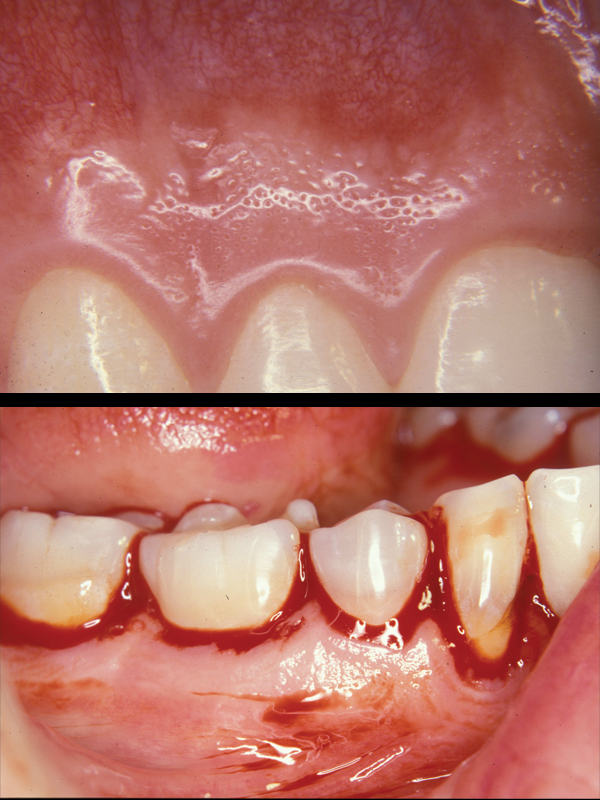

Gingivitis:

In health, the gum forms a crevice around the neck of a tooth. When bacterial plaque has not been adequately cleaned away from this crevice, the tissue becomes infected and swells. This tissue infection is called “gingivitis”. The tissue swelling deepens the normally shallow crevice, providing a larger “niche” for more bacteria, thus more infection.

Periodontitis:

If gingivitis lingers, this infection drips down onto the bone holding in your teeth and begins to dissolve it away. This advanced disease is called “periodontitis”. As the bone disappears, a deeper crevice, known as a “pocket”, forms around the teeth. These deep pockets serve as “larger & larger nests” where more and more bugs grow, perpetuating more bone loss and eventually tooth loss.